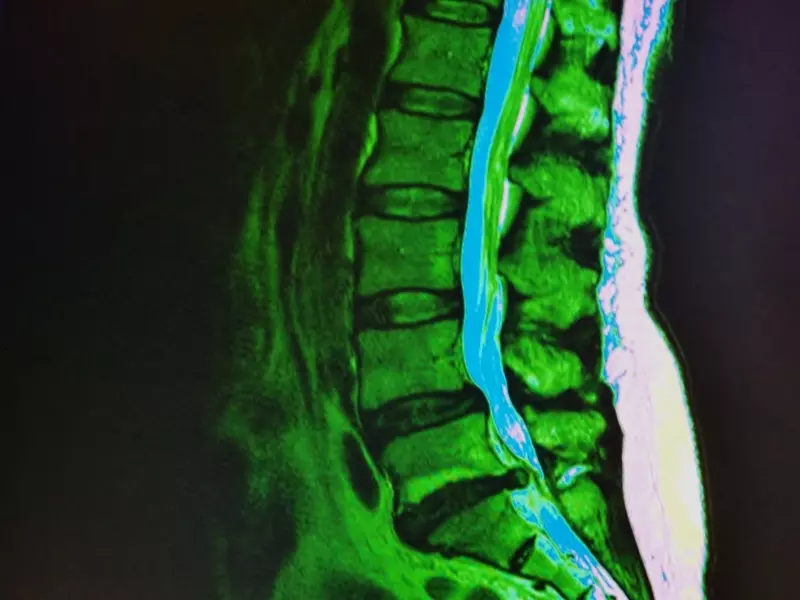

Przewlekły ból mięśniowo-szkieletowy zazwyczaj jest bólem nocyceptywnym. Jeżeli jednak w badaniu fizykalnym i badaniach obrazowych nie udaje się zaobserwować żadnych zmian patologicznych, możemy mieć do czynienia z bólem pochodzenia psychogennego.